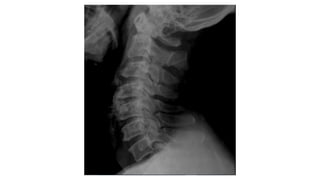

Anterior vertebral line

Posterior vertebral line

Spinal laminar line

Line across the spinous process

• #23 Ant vert body line Post vert body line Spinal laminar line Line across the spinous process

• #24 Too wide or narrow or uniform Too wide or parallel Too wide too narrow

• #27 dens occipital bone spinous process transverse band of t1 trachea first rib

• #28 Height of cervical bodies Height of each joint space Spinous process in alignment